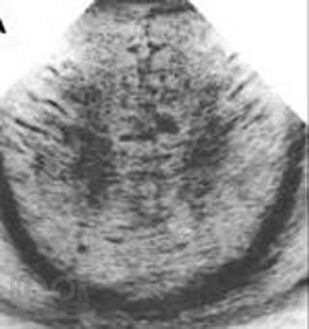

Это первая отечественная книга по патологии головного мозга у новорожденных и детей раннего возраста. Книга состоит из 7 глав, в которых рассмотрены вопросы развития головного мозга во внутриутробном периоде, этиология, патогенез, патоморфология и клинические проявления основных поражений мозга, а также внутричерепные кровоизлияния и пороки развития, в том числе уникальные. В книге также изложены новые и дискуссионные вопросы диагностики заболеваний, приведены классификации поражений, уточнены вопросы нозологии в детской неврологии, которые изучены недостаточно. Читатель получит сведения о том, насколько велико разнообразие форм поражений головного мозга у детей, как эти поражения отличаются от патологии мозга у взрослых и какова роль инфекций, гипоксии, родовой травмы и других факторов в их происхождении. Текст сопровождают более 450 цветных иллюстраций (фотографии, схемы и графики). Книга предназначена для патологов, педиатров, акушеров, перинатологов, инфекционистов, детских невропатологов, неонатологов, реаниматологов, специалистов нейровизуализационных методов исследования и судмедэкспертов. Книга может служить учебным пособием или справочником по основным заболеваниям головного мозга у новорожденных и детей раннего возраста.